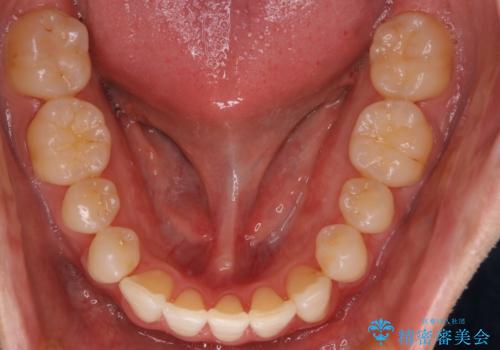

- 前歯の歯並びの改善を希望され来院された患者様です。

初診時の歯並びの状態としては、上下ともに前歯部の中等度のがたつきがあり、上の前歯が重なっている状態でした。

また元々下の前歯は1本少なく、歯の本数が少ないことを前提とした矯正治療を行いました。

抜歯は必要なく、マウスピース矯正にて治療を行っています。

見た目、嚙み合わせ及び、治療期間や施術内容に大変ご満足いただきました。